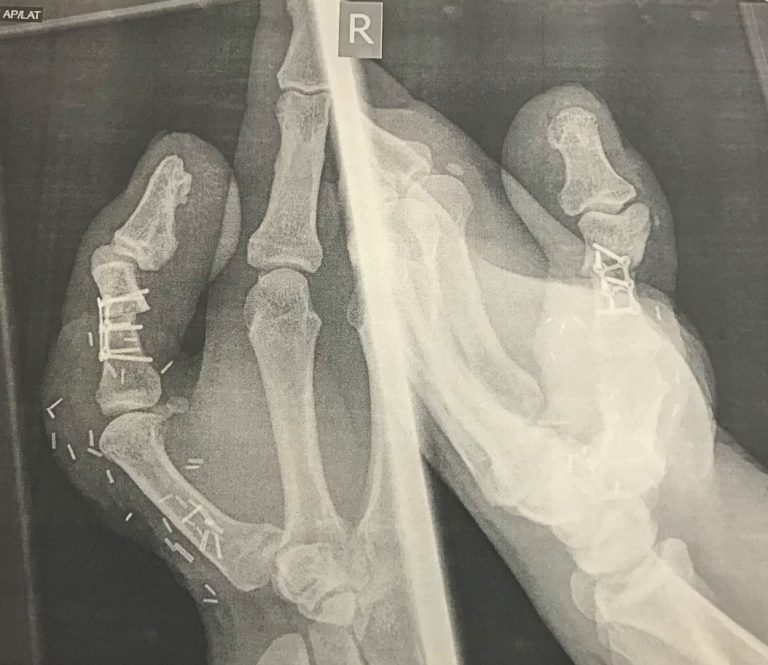

El 9 de enero de 2019, la mano derecha de David Lee quedó atrapada en un máquina que le trituró el dedo. Además del trauma de la pérdida de su dedo, el hombre temía no poder seguir ejerciendo su profesión, confección y arreglo de zapatos. La solución llegó de la mano del Hospital Universitario de Derby y Burton, lugar en el que hicieron efectivo un trasplante de su dedo gordo del pie a la mano

La operación, que duró diez horas fue acompañada de un largo proceso de recuperación, un año más tarde, David pudo retomar sus funciones normales en el trabajo.